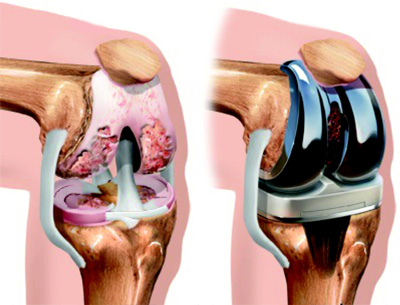

Endoprotezoplastyka (zastąpienie stawu sztucznym stawem) to bardzo skomplikowany i ryzykowny zabieg, który często prowadzi do różnych powikłań, w tym utraty samodzielności i niepełnosprawności.

Jeśli nie zostaną podjęte odpowiednie działania na czas, dochodzi do całkowitej utraty stawu. A jedynym rozwiązaniem jest operacja, podczas której staw zostaje zastąpiony sztucznym. Jednak nalegam, aby nie dopuszczać do takiego etapu. Sam zabieg wymiany stawu często kończy się infekcją, która może prowadzić nawet do amputacji dotkniętej części ciała!

Zdjęcie z operacji, podczas której staw został zastąpiony sztucznym stawem.

W 60–70% przypadków dochodzi do odrzucenia endoprotezy, co skutkuje nieznośnym, przewlekłym bólem oraz całkowitą utratą funkcji kończyny.